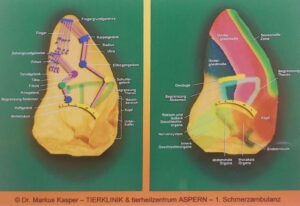

- Sviluppo di una mappa d’impianto personalizzata;

Identificazione del punto e piccola incisione con il bisturi

Posizionamento dell’ago cavo con infissione del grano d’oro